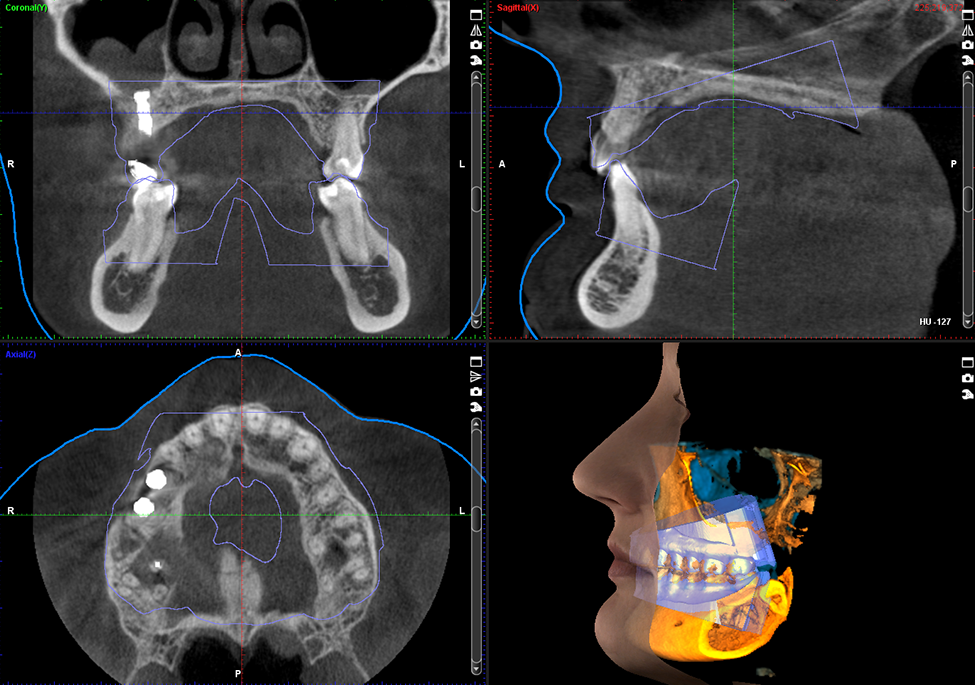

Questa immagine di seguito, mostra immagini 3D acquisite con un apparecchio TC Cone Beam.